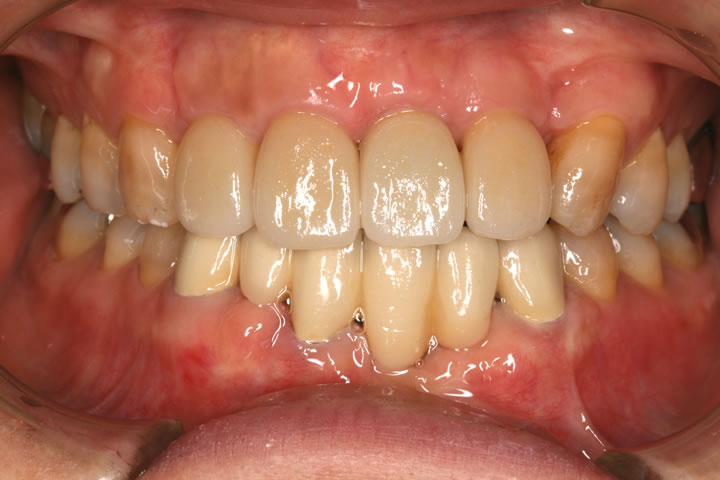

治療後

• 治療後

治療終了時の写真です。左上の前歯はインプラントになりました。

その他の前歯はラミネートべニアという治療方法できれいにしました。下の歯も陶器の歯でかぶせています。